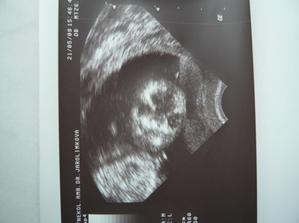

Tak se na nás snad už štěstí konečně usmálo a na IVF už nepůjdeme....... Měli jsme těsně před stimulkou na 2.IVF a čekali na mrchu. Místo toho jsme 15.3.2009 objevili naše krásné //. 17.03.2009 bylo na UTZ vidět plodové vejce, cca 2,7mm, další kontrola 31.3.2009. Tam už byl vidět náš bobeček, 6,3mm veliký a srdíčko mu bilo jako o závod. Dostali jsme krásné fotečky a jsme moc šťastní. Tak konečně je 23.4.2009 a jsme i s taťkou na dalším UTZ, jsme 9+6. Paní doktorka z nás měla velkou radost, říkala, že tak mrskající se miminko už dlouho neviděla. Velikostí odpovídáme úplně na den, máme už těhu průkajdu a dneska jsem se objednala na časný genet. skr. k MUDr. Břešťákovi. Termín porodu je 20.11.2009 a manža má narozky 24.11. 2009. No a já je mám zítra, takže super dnešní dárek. Tak dneska 11.5. 2009 jsem byla u zubaře pro razítko do těhu průkajdy a už ho mám. Další den 12.5.2009 jsme byli u mé praktické paní doktorky, natočila mi EKG a dala nám razítko do těhu průkajdy. Dneska 14.5.2009 jsme byli s manžílkem na genetickém screeningu. Pan doktor a sestřička byli moc hodní. Sestřička mi nabrala krev, vůbec jsem nezaznamenala, že je po odběru, je moc šikovná. Výsledky budou do 14-ti dnů. Pan doktor nám ukázal miminko v celé své kráse, jsme obříci, máme skoro 8 cm, NT 1,8 mm. Dle pana doktora jsme o 6 dnů větší a odpovídáme 13+5 (dle MS 12+6), tak nám upravil termín porodu na 14.11.2009. Slyšeli jsme tlukot srdíčka a bylo to nádherné, 160 úderů /min.. Pan doktor nám dal fotečky na CD, tak jsme moc šťastní. Jelikož nám pan doktor posunul termín porodu o týden dříve, tak jsme se byli 19.05.2009 zaregistrovat k porodu do FN Motol. Dneska 21.05.2009 jsme byli na kontrole a dostali jsme fotečky obličejíčka našeho mimíska. Je to celý tatínek. Mimísek na nás koukal a pěkně skotačil, paní doktorka nám ukázala jak má právě nožičku u hlavičky. Na den dětí 01.06.2009 jsme se dozvěděli, že výsledky screeningu jsou v pořádku. Jsme moc rádi. Dne 04.06.2009 jsem si volala na výsledky krevních triple testů a sestřička mi sdělila, že jsou v pořádku. Jsme s taťkou moc šťastní. Tak dneska 11.06.2009 jsme byli na kontrole u naší paní doktorky a s taťkou jsme byli zvědaví, jestli se nám už ukáže holčička nebo chlapeček. Paní doktorka se moc snažila, říkala, že by to viděla na holčičku, ale že opravdu spíše tipuje, protože miminko nechtělo roztáhnout nožičky. Tak uvidíme, jestli nám to řekne pan doktor na velkém UTZ, kam se objednáme. Bylo vidět, jak si miminko podpírá ručičkou bradičku a paní doktroka nám udělala nějaké fotečky. Jsme s tatínkem moc rádi, že se má miminko fajn. Dneska končíme 4. měsíc. Po měsíci -7.7.2009 jsme konečně zase viděli naše miminko. Paní doktorka nám ukázala močový měchýř, srdíčko, žaludek. Miminko se mrskalo, dokonce nám zamávalo. Paní doktorka nám řekla, že na 90% čekáme holčičku!